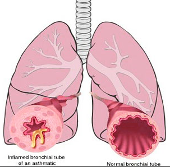

₦48,000.00Asthma - With combine herbs, the treatment is designed in aiding the diseases of the bronchial tubes.